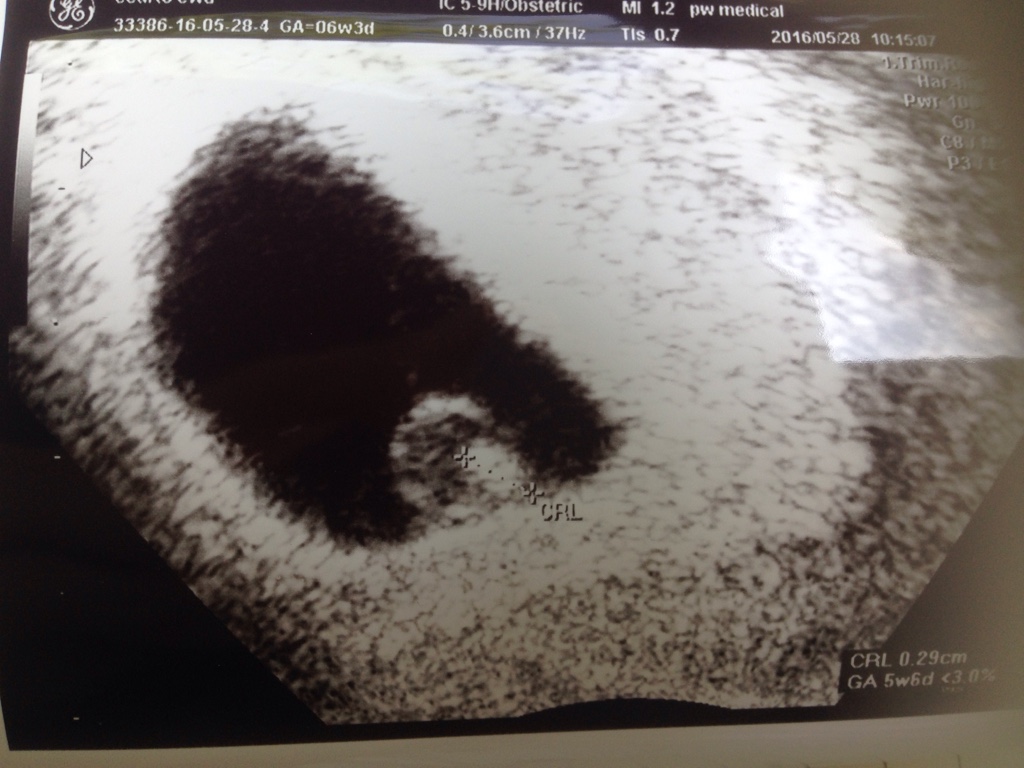

Chcialam Wam przedstawim nasze malenkie szczescie [emoji7]

1464459153-su1eey.jpeg

W dzidzia wszystko super! Wiedzielismy i slyszelismy serduszko!!! Ja do tej pory jestem w szoku i pod wrazeniem, ze na prawde widzialam pulsowanie i slyszalam je [emoji1] niesamowite!!!